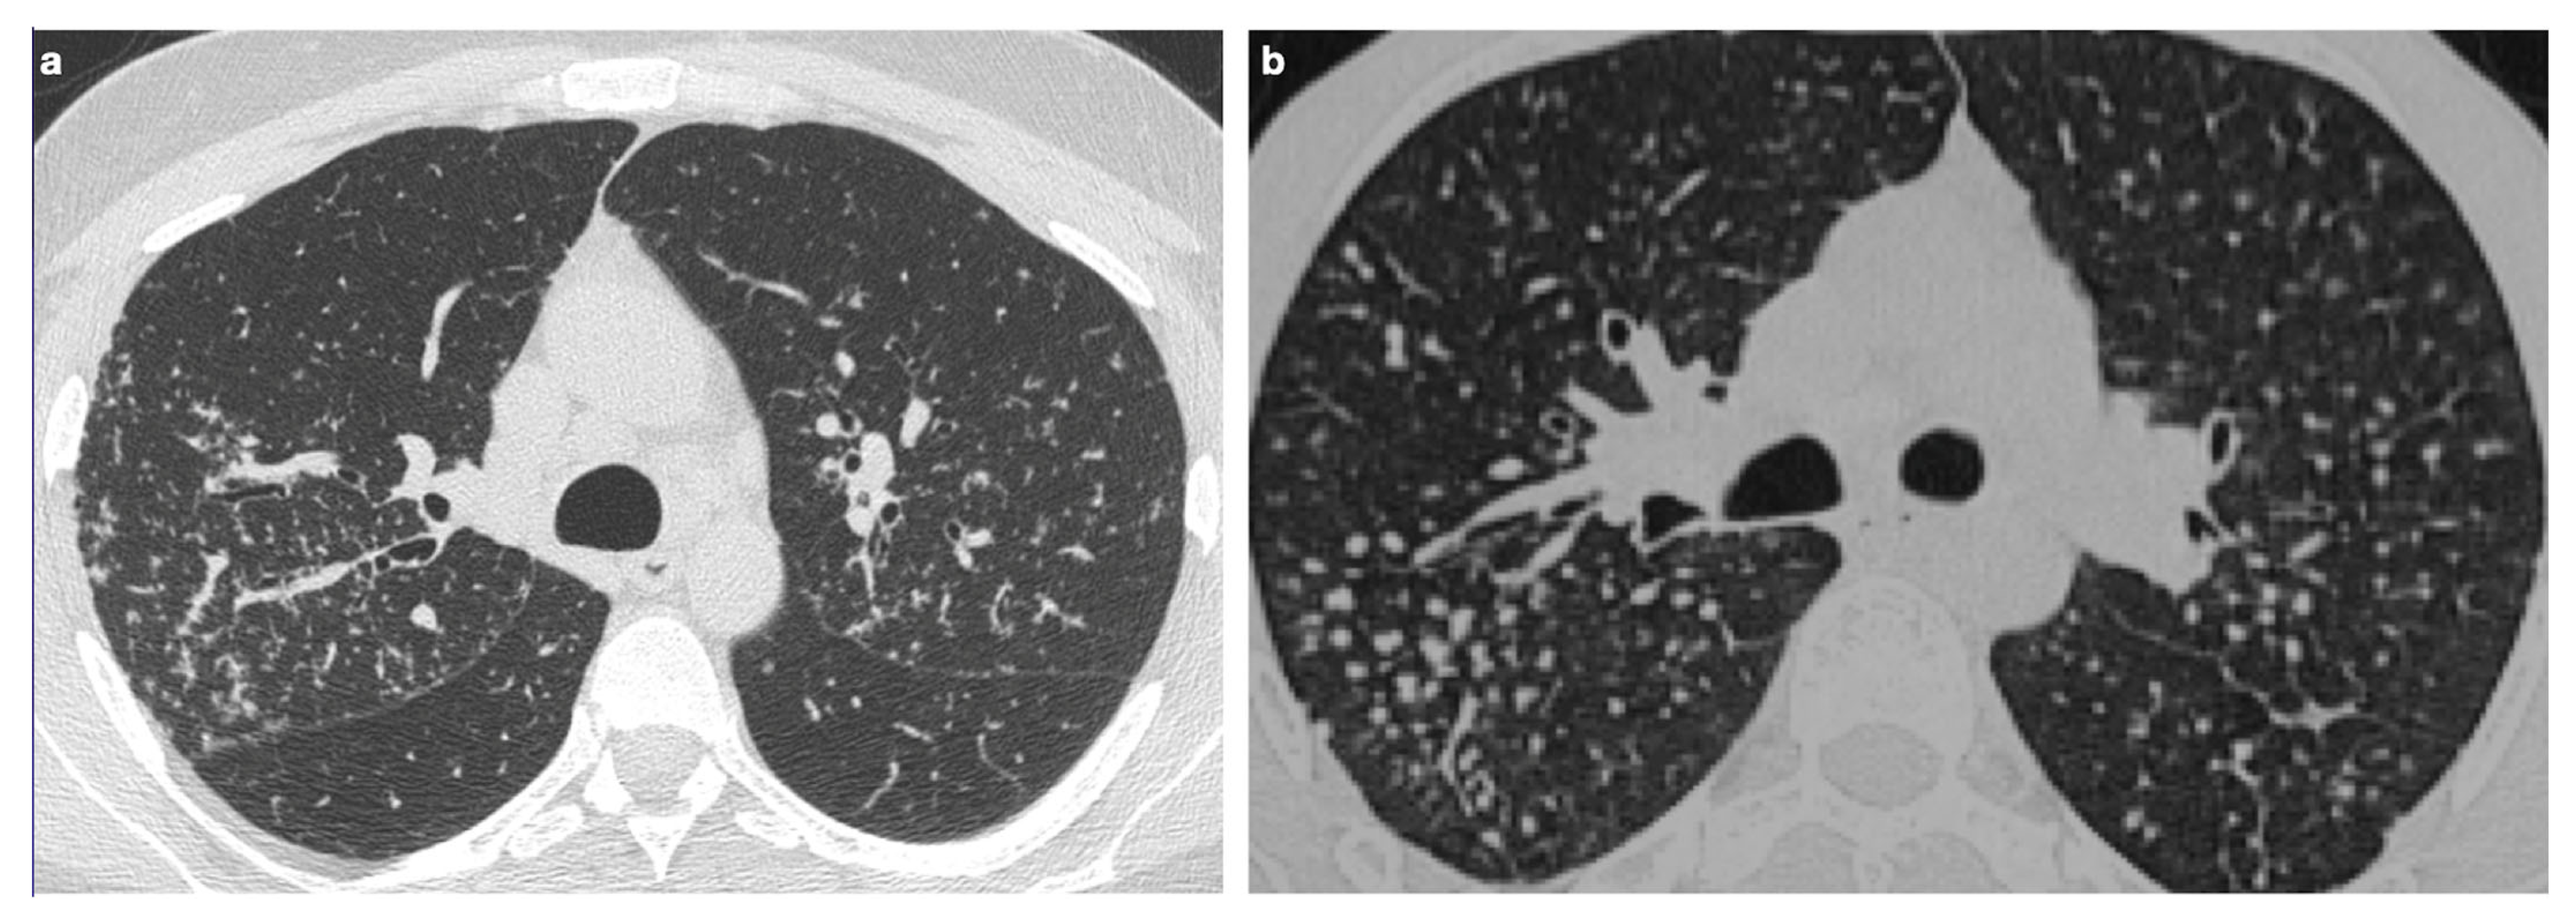

4. Pulmonary Interstitium

4.1. Typical Imaging

| Characteristic | Description |

|---|---|

| Distribution | Perilympathic (75–90% of cases); bilateral and symmetric involvement, especially in the middle and upper lobes |

| Nodule size | Micronodules 2–4 mm in diameter |

| Morphology | Nodules with well-defined margins, round shape |

| HRCT localization | Peribronchovascular interstitium, interlobar fissures, interlobular septa |

| Evolution | Possible coalescence of micronodules into macronodules over time |